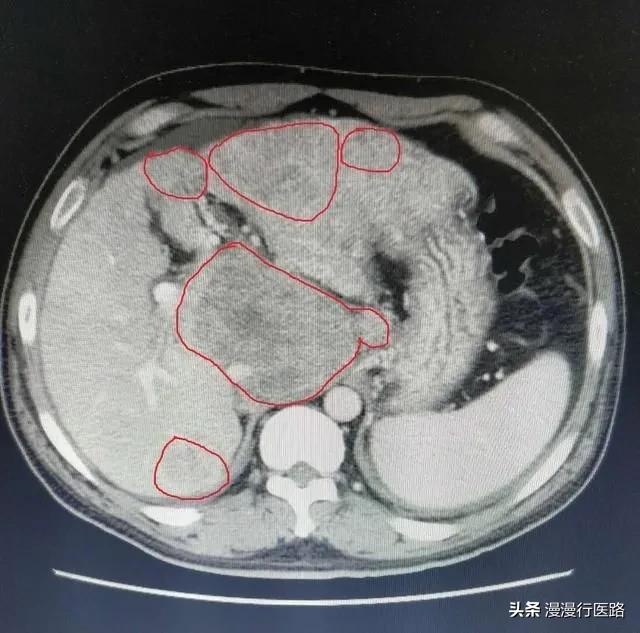

CTでは肝臓外縁に波状の変化を認める。肝裂孔が広がっている。脾臓はわずかに腫大している。

肝臓の形態

超音波やCTで肝臓の形状を確認することができる。重症の肝硬変では、肝臓の萎縮がみられ、肝臓の表面にはギザギザや波状、鈍化した縁のような明らかな凹凸があり、肝実質のエコー原性が不均一に亢進し、通常は肝静脈の菲薄化、ねじれや不均一な厚みを伴い、腹腔内には複数の液状の暗色部がみられる。